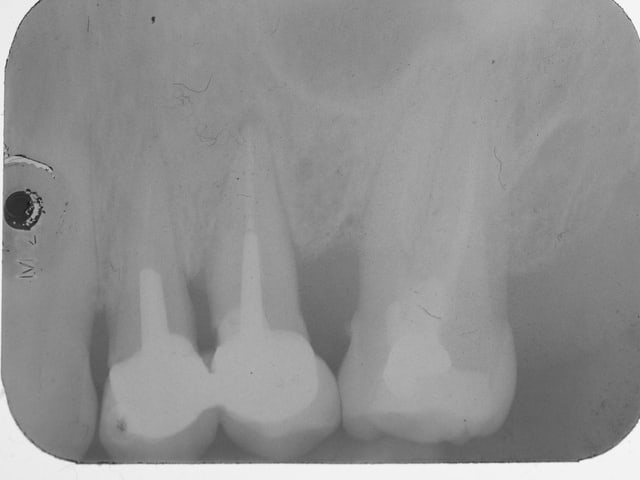

comme promis resto-radio

ci joint 2 radios de controle a 10 ans .

pas de resorption au tiers apical pas d ankylose .